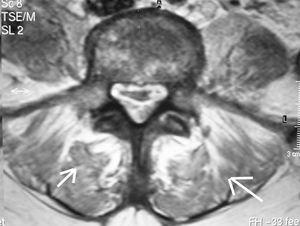

Se trata de una mujer de 69 años con antecedentes de diabetes mellitus tipo 2, mastectomía radical izquierda por carcinoma de mama, que recibió quimioterapia, radioterapia y hormonoterapia con tamoxifemo. Se encontraba en tratamiento con insulina NPH y tamoxifeno. Acudió al servicio de Urgencias de un hospital de nuestra área sanitaria con clínica de dolor lumbar de 5 días de duración. Había presentado leucocoria de ojo izquierdo en las últimas 48 horas. En la exploración física presentaba temperatura de 37 ºC, leucocoria de ojo izquierdo y dolor a la palpación sobre las últimas vértebras lumbares. La tensión arterial era de 160/90 mmHg, frecuencia cardíaca 110 latidos/minuto y frecuencia respiratoria de 28 respiraciones/minuto. La analítica mostró: hemoglobina: 12,3 g/dl, hematocrito: 34,5%, leucocitos: 16.900/mm3 (el 95% segmentados, el 3% cayados), plaquetas: 67.000/mm3, actividad de protrombina: 83%, tiempo de cefalina: 29 seg, glucosa: 576 mg/dl, urea: 122 mg/dl, creatinina: 1,2 mg/dl. La gasometría arterial (fracción inspirada de oxígeno [FiO2] 0,35) mostró: pH: 7,42, presión parcial de dióxido de carbono arterial (PaCO2): 37 mmHg, presión parcial de oxígeno arterial (PaO2): 81 mmHg, bicarbonato: 24 mEq/l. En el sedimento de orina destacaba intensa bacteriuria. La radiografía de tórax fue normal. Durante su estancia en Urgencias sufrió deterioro neurológico por lo que se realizó una tomografía axial computarizada de cráneo que no demostró patología intracraneal, presentando aumento de la densidad de cristalino izquierdo. Se realizó punción lumbar que resultó de aspecto purulento con resultado siguiente: leucocitos: 168.000 mm3 (el 83% segmentados), glucosa: 43 mg/dl, proteínas: 2.350 mg/dl y cocos grampositivos. Se diagnosticó de meningitis e infección del tracto urinario y se trasladó a nuestra Unidad de Cuidados Intensivos (UCI). Se inició terapia antibiótica empírica con ceftriaxona y vacomicina. Ante la presencia de importante dolor lumbar se realizó resonancia magnética nuclear (RMN) de columna dorso-lumbar que evidenció la presencia de espondilitis a nivel de L4 y L5 con una colección en espacio epidural compatible con absceso epidural (fig. 1) y afectación de ambos músculos psoas (fig. 2). Fue intervenida con desbridamiento de los abscesos de músculos psoas tomando muestras para análisis microbiológico. También se obtuvieron muestras de humor vítreo y se instilaron antibióticos intraoculares. Se aisló en cultivo de líquido cefalorraquídeo, hemocultivos, cultivo de orina, humor vítreo y muestras de pus de psoas S. agalactiae sensible a penicilina, por lo que se sustituyó el tratamiento antibiótico mencionado por penicilina G endovenosa; por parte de oftalmología se instauró tratamiento con vancomicina y ceftriaxona en colirio.

Figura 1. Resonancia magnética nuclear de columna dorso-lumbar que evidencia la presencia de espondilitis a nivel de L4 y L5, además de un absceso epidural.